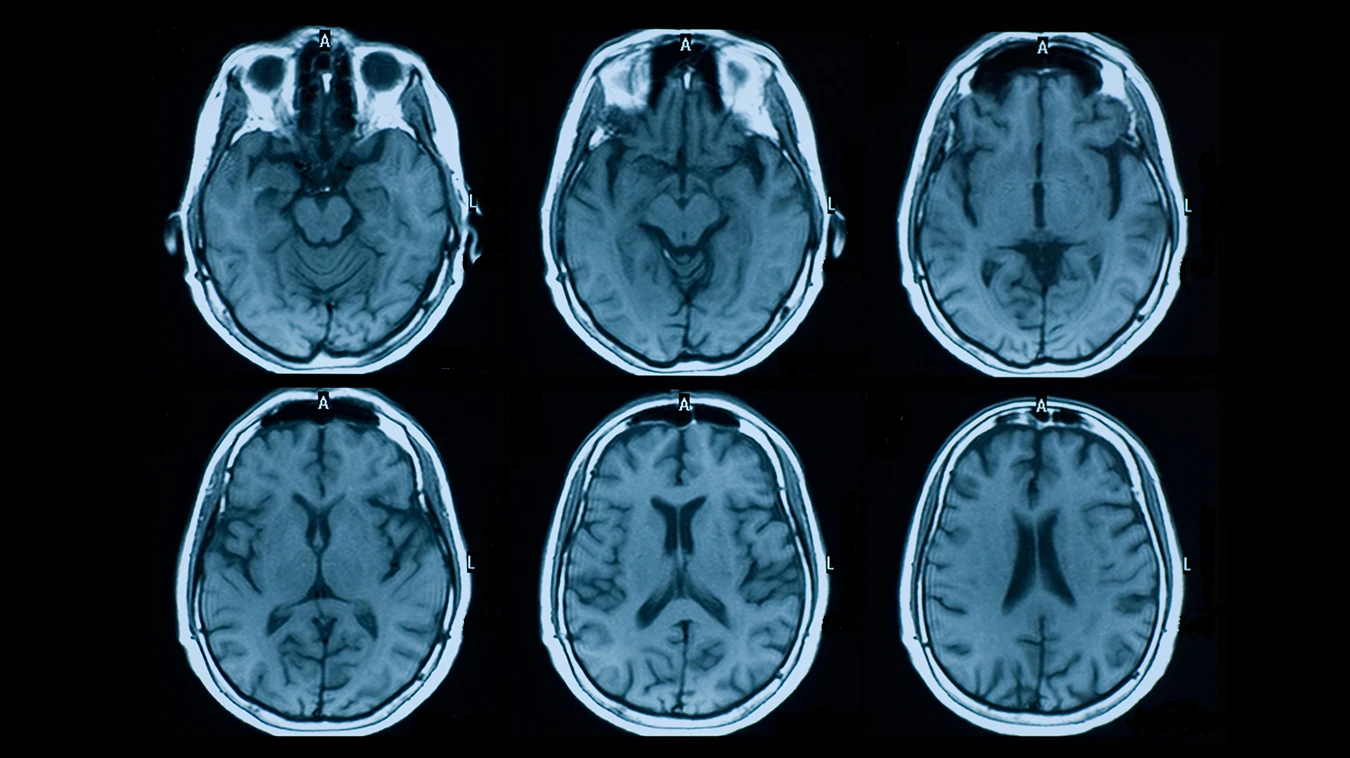

يقوم طبيب الأمراض النفسية والعصبية أو المخ والأعصاب بتشخيص هذا المرض بناءً على نتيجة إشاعات الرنين المغناطيسي على المخ والفقرات العنقية والظهر بالكامل ونتيجة تحليل بذل النخاع الشوكي ووظائف الكلى والكبد وتحليل الدم، ويقوم المريض بعمل تلك الفحوصات بعد أن يقوم الطبيب بالفحص السريري، وفي حال كان الشخص مصاب بالتصلب المتعدد تظهر في الإشاعات بعض البؤر على المراكز العصبية سواء في المخ أو النخاع الشوكي.